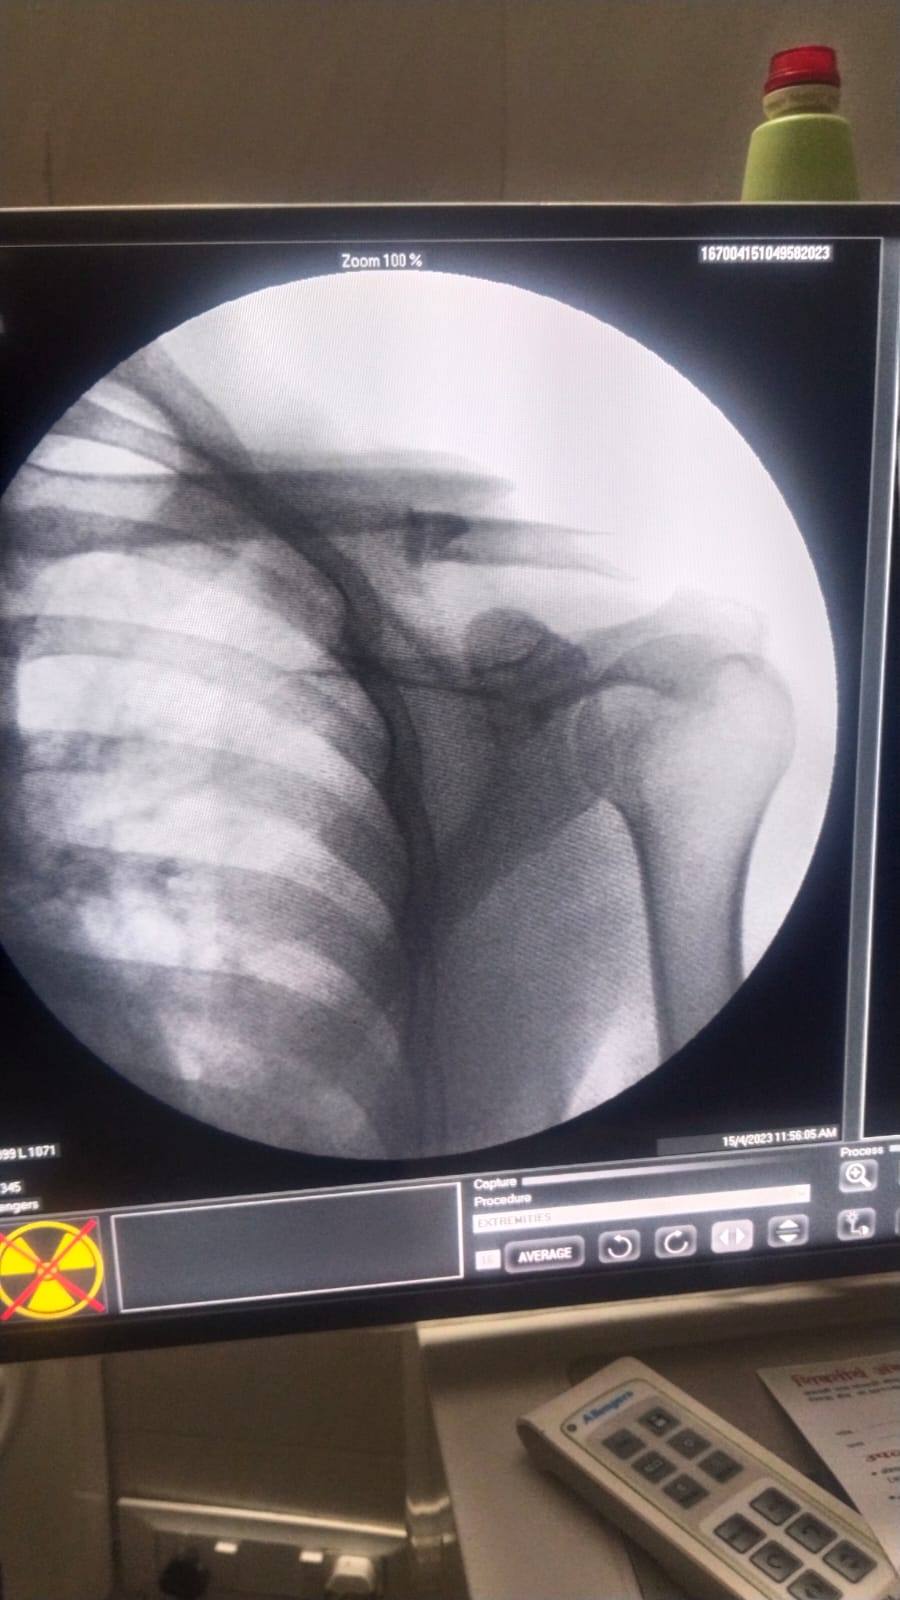

Shoulder dislocation and unable to raise this hand comfortably.